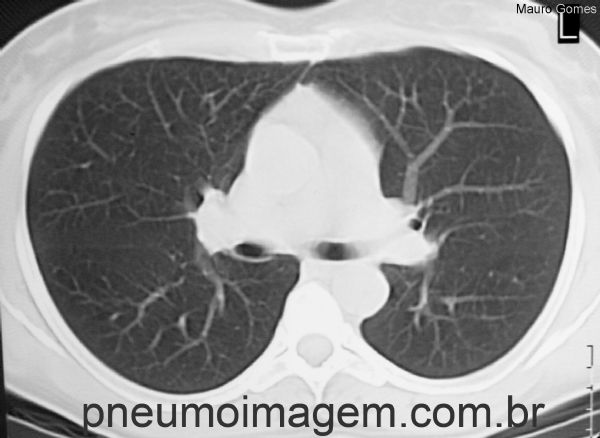

Mesmo paciente em corte tomográfico realizado na mesma altura da imagem anterior e após a suspensão da droga e uso de corticóide. Houve regressão total das lesões pulmonares.

Tomographic slice performed in the same area the previous image. After suspension of the drug and use of corticoid, there was a total regression of the lung lesions.